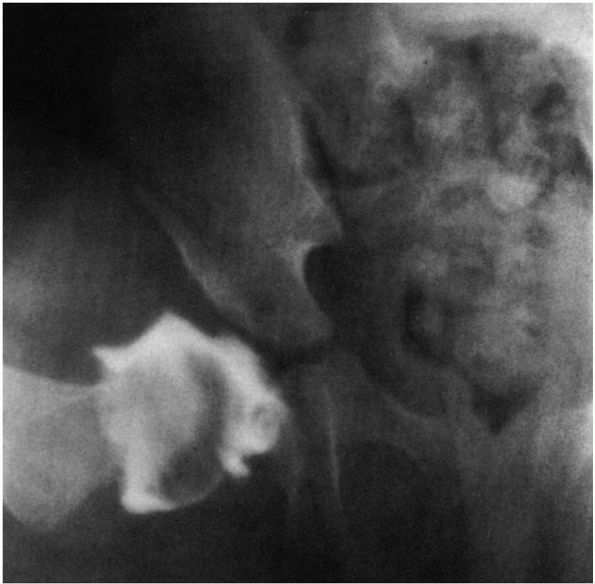

room setting. Under general anesthesia, the hip is gently manipulated

into the acetabulum. Arthrography is extremely helpful in assessing the

adequacy of reduction (Figure 15-10). Because a

large portion of the acetabulum is cartilaginous, the relations of the

femoral head and acetabulum are nicely visualized on arthrography. The

use of arthrography can help to assess any obstacles to reduction and

![]() |

|

FIGURE 15-10. Attempted closed reduction under arthrographic control. Note pooling of dye medially. The hip cannot be reduced.